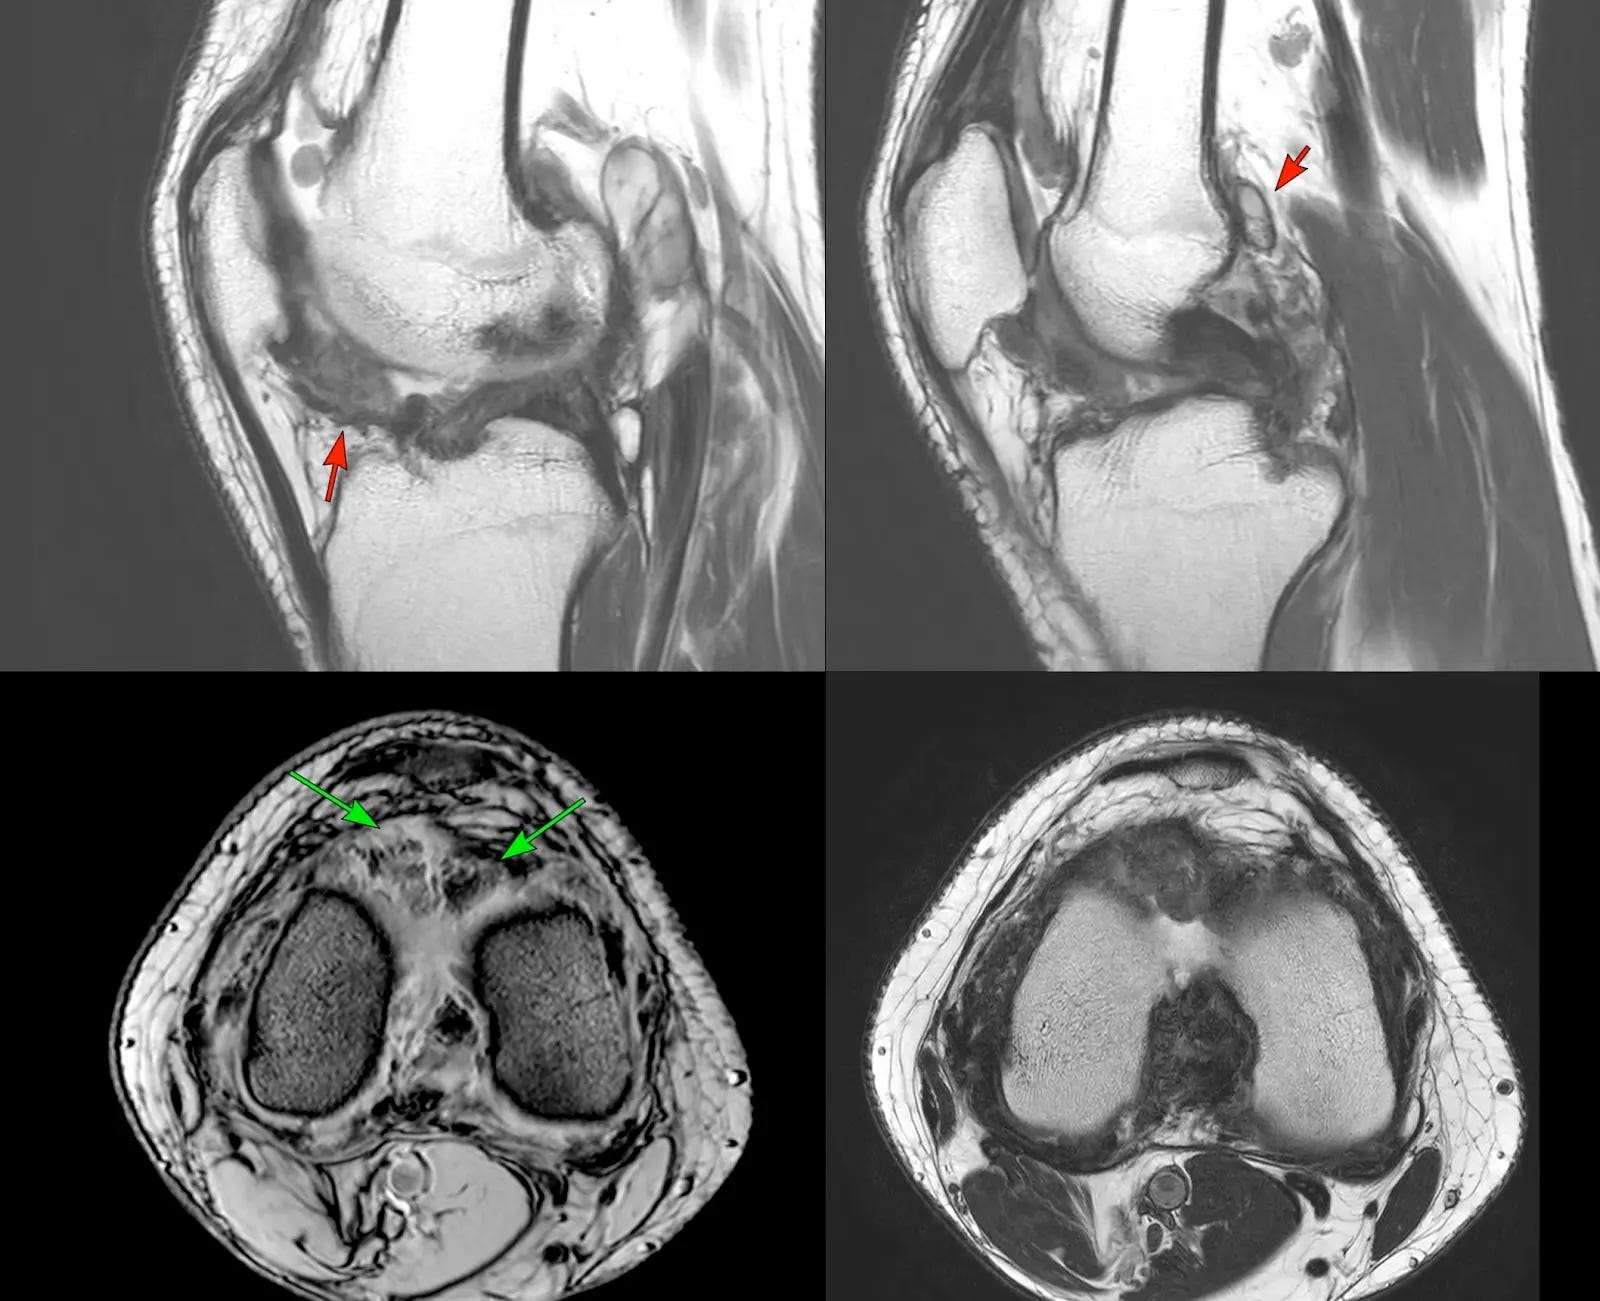

Case:

23-years old known to have tenosynovial giant cell tumor - the gradient image (lower left image) shows blooming of hemosiderin (green arrows).

The nodular synovitis is T2 dark in the sagittal and axial images. This used to be earlier called pigmented villonodular synovitis (PVNS).